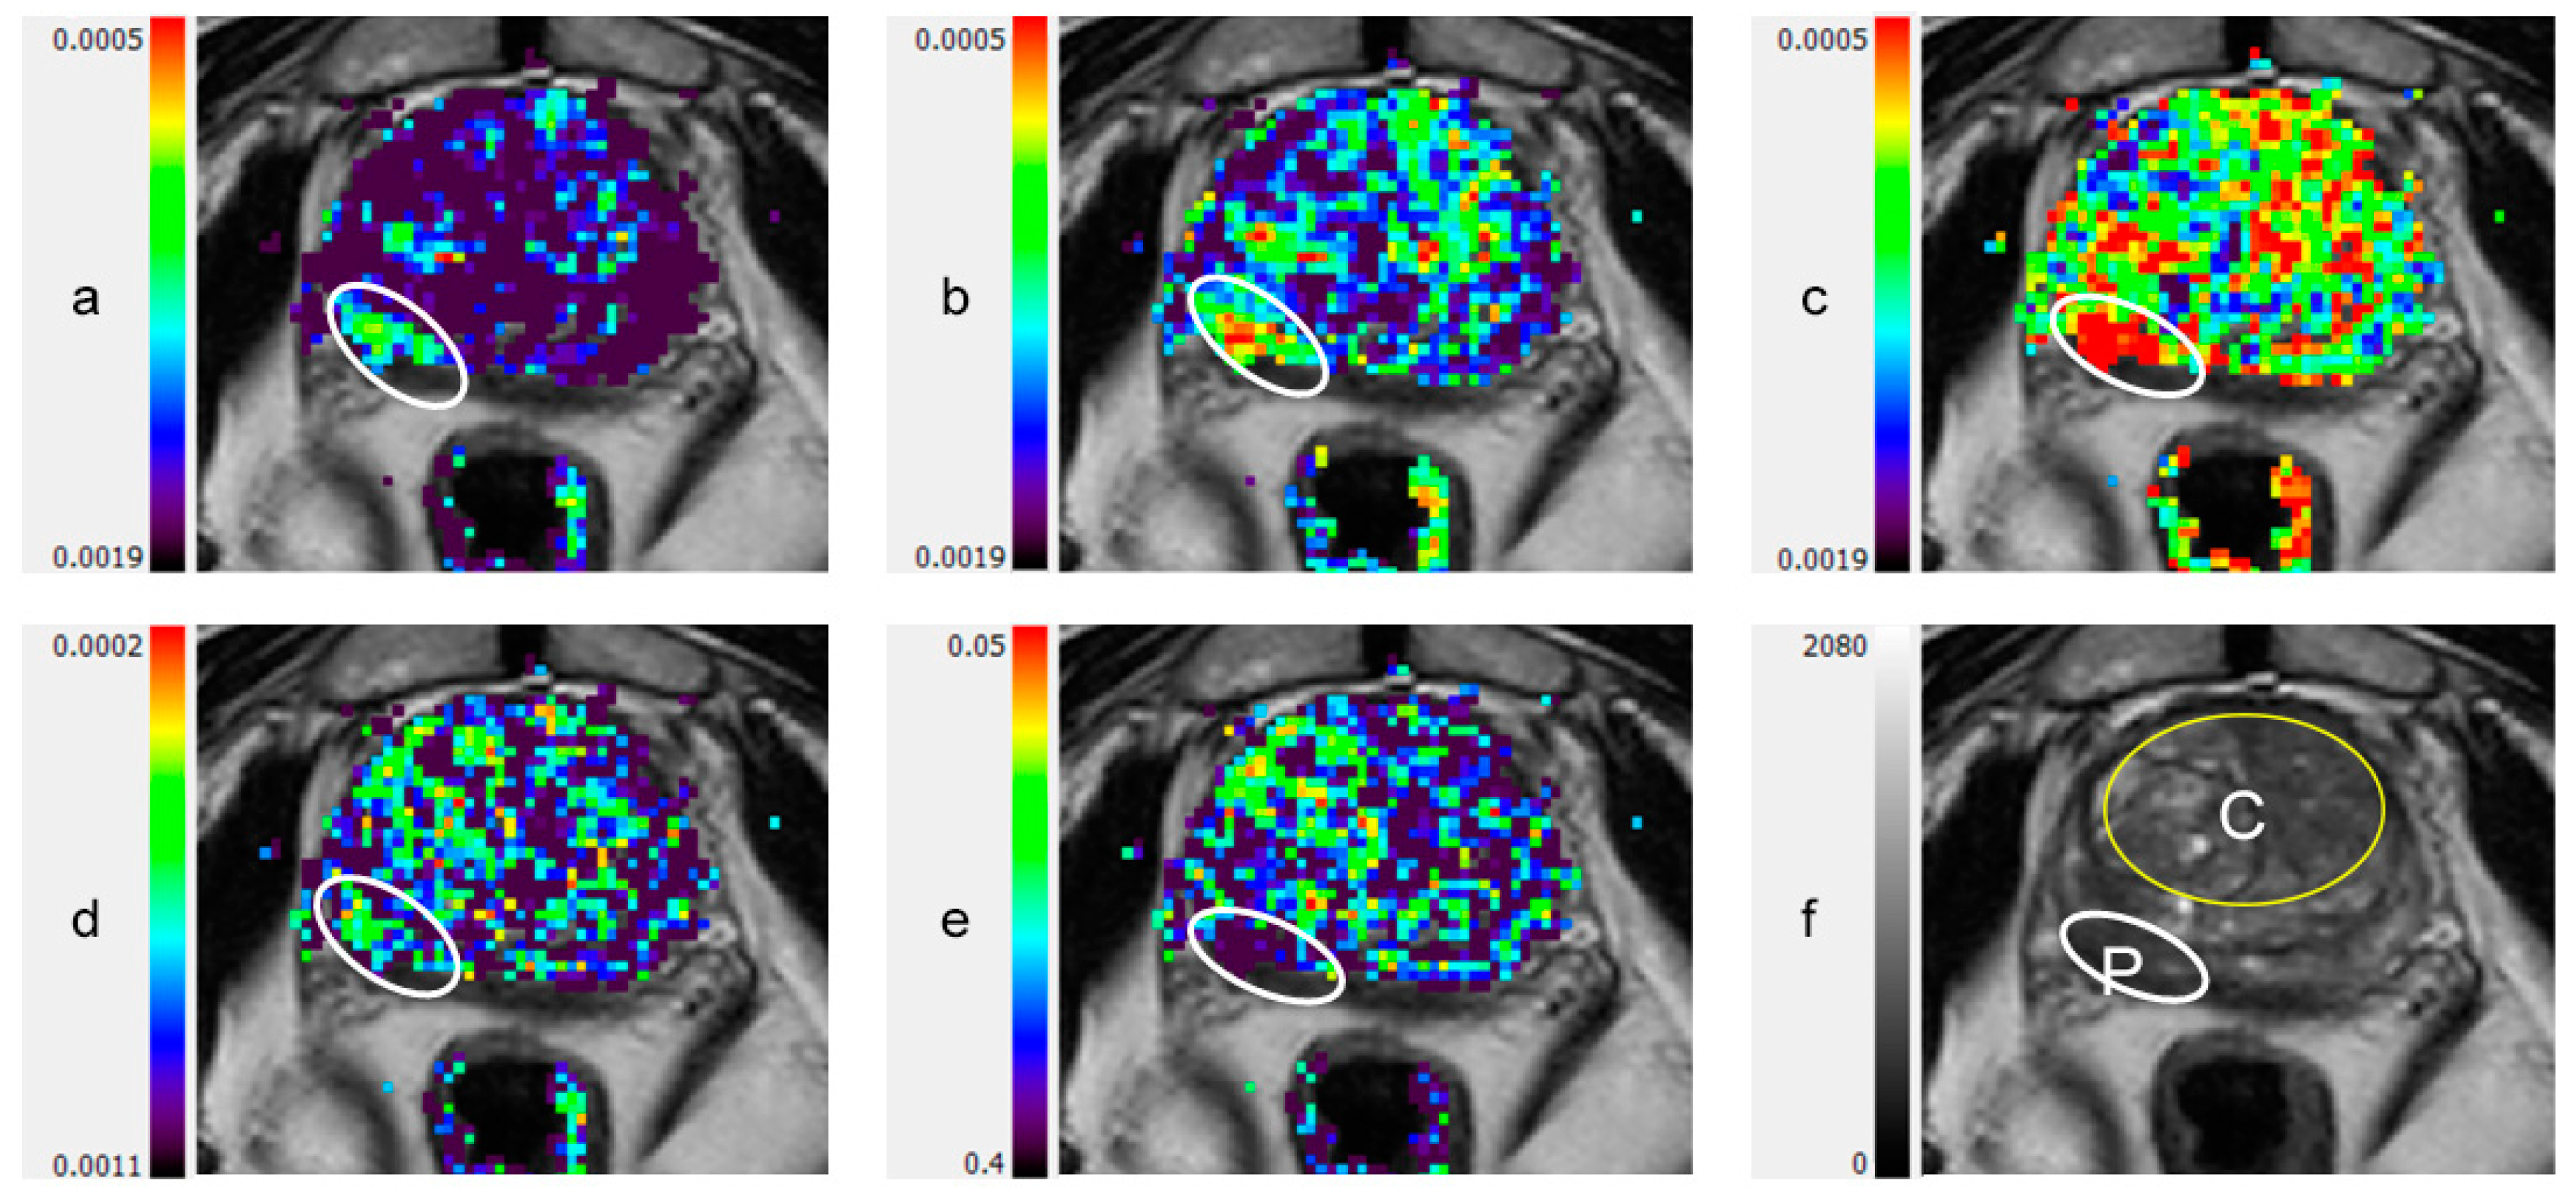

2.5. DTI Image Processing and Analysis

3.2. DTI Metrics